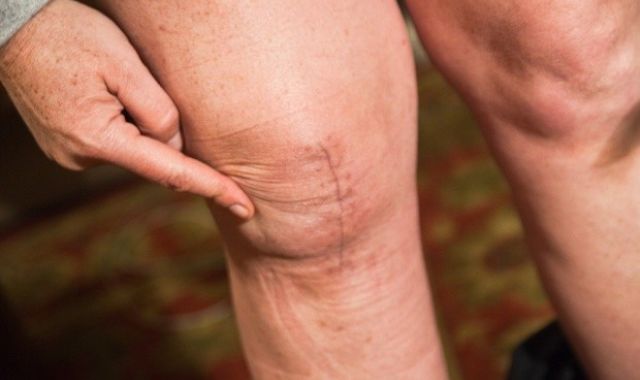

What Can Go Wrong with Knee Replacement????

Most knee joint operations are problem-free but about 1 person in every 20 may have...